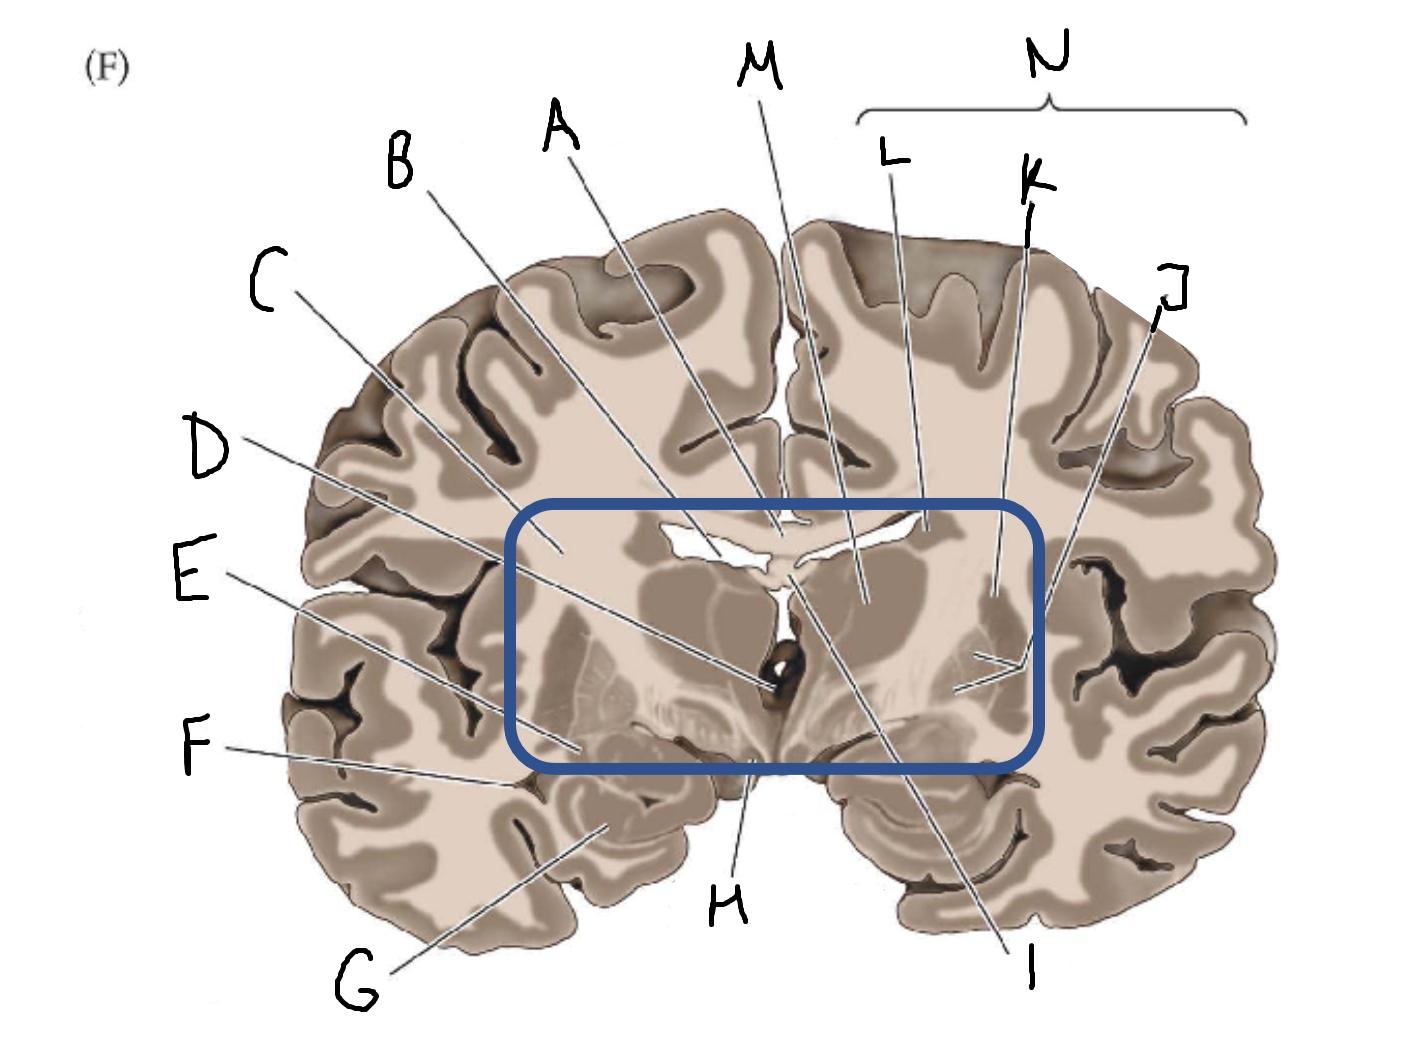

A

corpus callosum

B

lateral ventricle

C

internal capsule

D

third ventricle

E

tail of caudate nucleus

F

lateral ventricle

G

hippocampus

H

mammillary body

I

fornix

J

globus pallidus

K

putamen

L

caudate

M

thalamus

N

basal ganglia